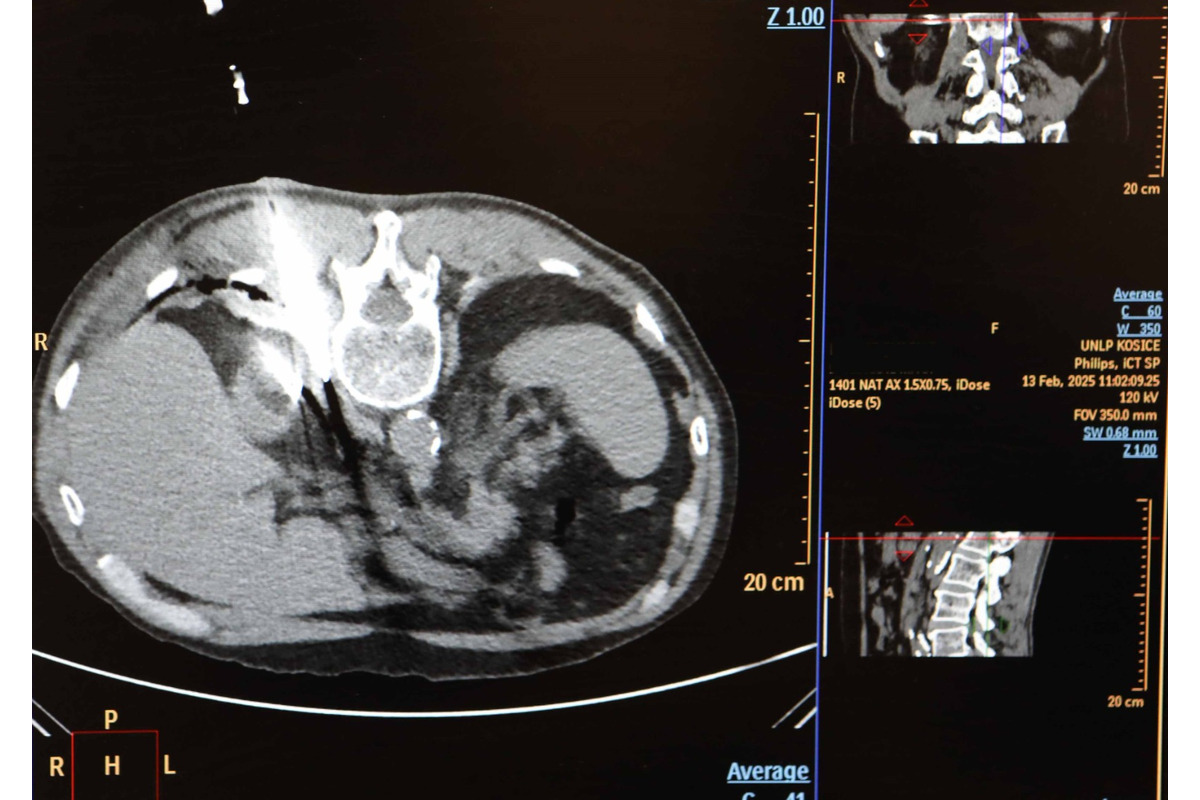

FOTO: Košická univerzitná nemocnica zaviedla pokrokovú liečbu tumorov

FOTO: Košická univerzitná nemocnica zaviedla pokrokovú liečbu tumorov, foto 8

Zdroj: UNLP